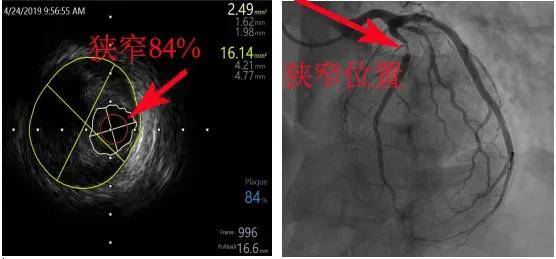

医学影像技术的进步为支架再狭窄的诊断和治疗提供了有力支持,光学相干断层扫描技术(OCT)、血管内超声(IVUS)等高精度影像技术能够准确评估支架内的情况,新型影像技术如核磁共振成像(MRI)和计算机断层扫描(CT)也为支架再狭窄的评估提供了更多可能。